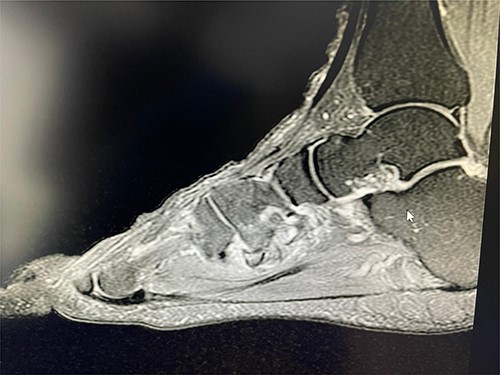

Based on this examination, the initial impression was tendinosis of the flexor hallucis longus. To confirm this diagnosis and rule out any other bony injury, a magnetic resonance imaging scan was requested of the right foot and ankle. Imaging revealed an avulsion of peroneus longus tendon at base of first metatarsal with a possible non-union as well (Figs 1–3).

Coronal T2 view showing the non-union of the first metatarsal avulsion fracture.